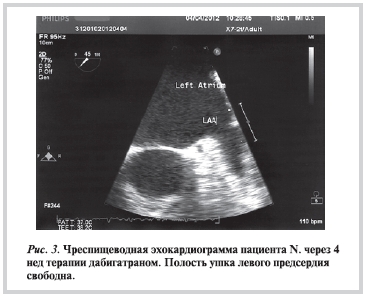

Больной продолжал получать АК, другие назначенные препараты. При повторной ЧП-допплер-ЭхоКГ, проведенной через 4 нед постоянного приема дабигатрана, посторонних включений в камерах сердца не обнаружено, умеренно выражено спонтанное контрастирование в полости и УЛП (рис. 3). Была произведена успешная электрическая кардиоверсия, назначена терапия для удержания синусового ритма.